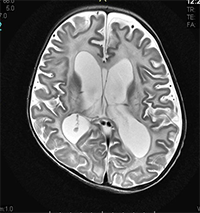

A 2 year old boy came with progressive enlargement of head, and regression of milestones. On examination, he was irritable and macrocephaly and spasticity in all 4 limbs. His radiological investigations are attached.

- What is the name of 2nd investigation shown and what does it show

- What is the likely diagnosis

- What is the MRI pattern in basal ganglia in this disease